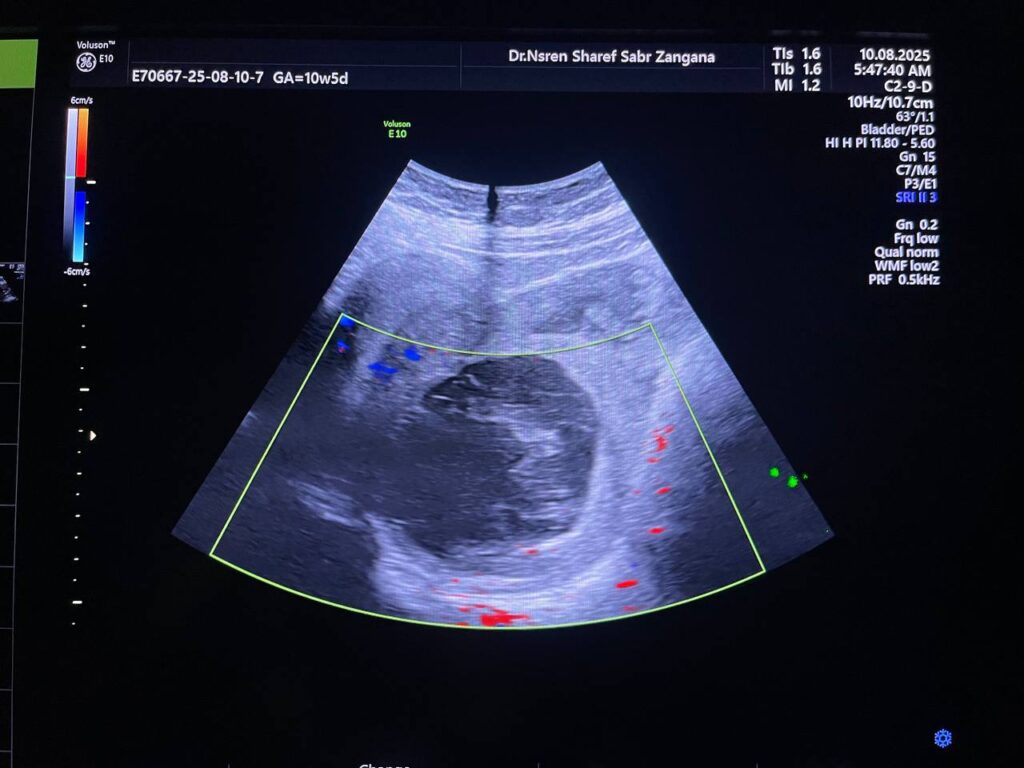

Right ovarian heterogeneous circumscribed avascular cystic mass its size 55x55mm, mostly hemorrhagic , with whirlpool sign , picture mostly of Twisted right hemorrhagic ovarian cystic , Cystic TORSION , please for further study ??

· No free pelvic fluid seen